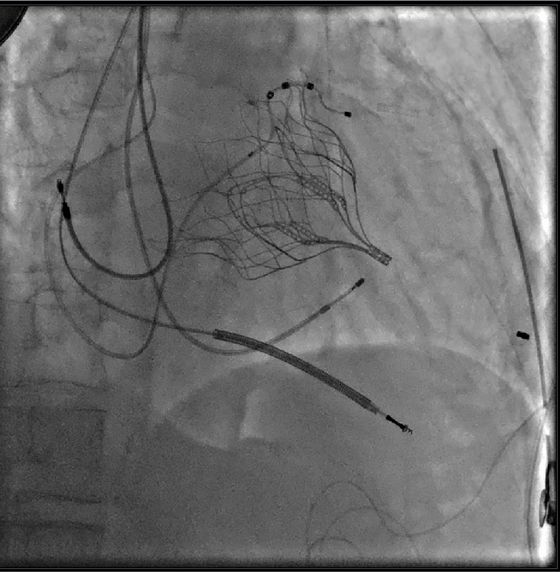

Erstmals in Brandenburg konnte die Tendyne-Technik zum Mitralklappen-Ersatz im Katheterverfahren erfolgreich eingesetzt werden.

Am Immanuel Herzzentrum Brandenburg wurde erstmals in Brandenburg ein Hochrisiko-Patient mit Mitralklappeninsuffizienz mit einem neuen Klappenersatzverfahren behandelt. Mithilfe einer „Tendyne-Klappe“ haben die Bernauer Herzspezialistinnen und Herzspezialisten dem Patienten im Katheterverfahren erfolgreich eine neue Herzklappe eingesetzt. Die neue Technologie ist die erste Behandlungsmöglichkeit ihrer Art, um die Mitralklappe ohne Operation am offenen Herzen zu ersetzen, wenn eine Transkatheter-Reparatur der Klappe nicht möglich ist. Der mehrfach vorerkrankte Patient, bei dem die Mitralklappe nicht mehr vollständig schloss, konnte so ohne Herz-Lungen-Maschine und Öffnung der Brust behandelt werden.

„Immer wieder hat die Herzmedizin verschiedenste Ansätze bei ausgewählten Patienten erprobt, aber keine konnte wie die TAVIs überzeugen“, so Prof. Dr. Butter. Mit der seit 2020 zugelassenen Tendyne-Ersatzklappe kommt ein neuer Verankerungsmechanismus zur Anwendung. Ein an der Klappe befestigtes Halteband (Klappen-Tether) wird mit einem kleinen „Knopf“ mit der Herzspitze verbunden und hält so die Klappe in Position. Die zarte künstliche Klappe selbst ist wie eine Doppelkrone in eine etwas größere tulpenförmige Halterung eingenäht. Sobald sie am Faserring, dem Übergang zwischen den Herzkammern, freigesetzt wird, dehnt sie sich aus und dichtet als neue Klappe den Ring ab.

Diese neue Technologie war die einzige Chance für den Patienten in Bernau. Nach gründlicher Vorbereitung setzte der leitende Oberarzt der Abteilung Herzchirurgie, Dr. Michael Erb, einen circa sieben Zentimeter langen Schnitt zwischen den linken Rippen. Durch die Öffnung konnte der Katheter durch die Herzspitze ins Herz bis zur undichten Mitralklappe vorgeschoben werden. Unter echokardiographischer Steuerung durch Dr. Tanja Kücken, Oberärztin der Abteilung für Kardiologie, setzen Prof. Butter und Dr. Michael Neuß, Oberarzt der Abteilung für Kardiologie, die neue Klappe genau an der richtigen Stelle frei. Sie nahm ihre Ventilfunktion sofort problemlos auf.